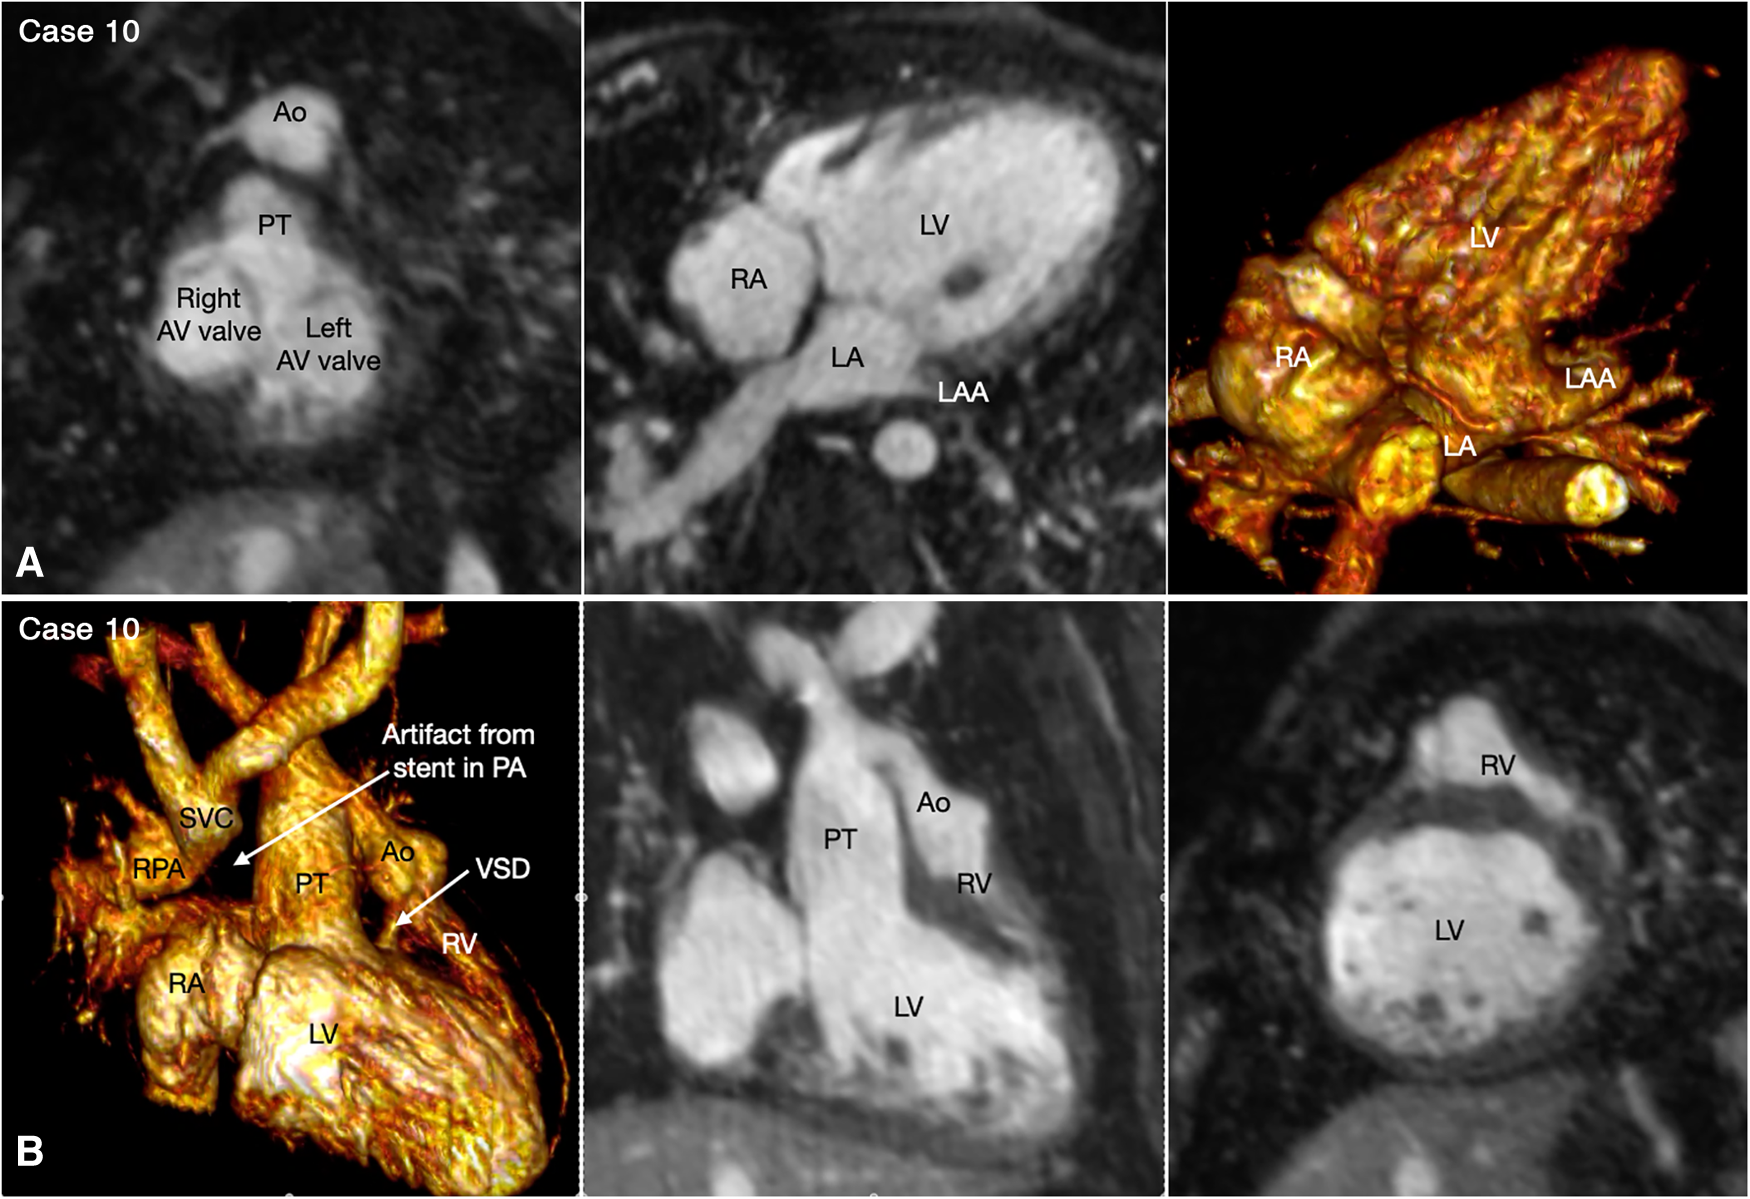

Figure 10

(Case 10). Double inlet left ventricle with discordant ventriculoarterial connection, status post Damus-Kaye-Stensel (DKS) procedure and aortic arch reconstruction followed by bidirectional cavopulmonary anastomosis. A short-axis maximum intensity projection (MIP) image (A-left panel) shows equally sized right and left atrioventricular (AV) valves. MIP image in an oblique axial image and volume rendered (VR) image taken in a similar view (A, middle and right panels) show that both atria are connected to the main chamber of left ventricular morphology (LV). VR and MIP images taken in a right anterior oblique projection and a short-axis MIP image in (B) show that the incompletely formed, hypoplastic right ventricle (RV) is located superiorly and to the left in relation to the left ventricle. The ventricular septal defect (VSD) is very small. The native aorta (Ao) arises from the right ventricle and the native pulmonary arterial trunk (PT) arise from the left ventricle. The aortic valve and root are located at the left and anterior aspect of the pulmonary valve and arterial trunk.